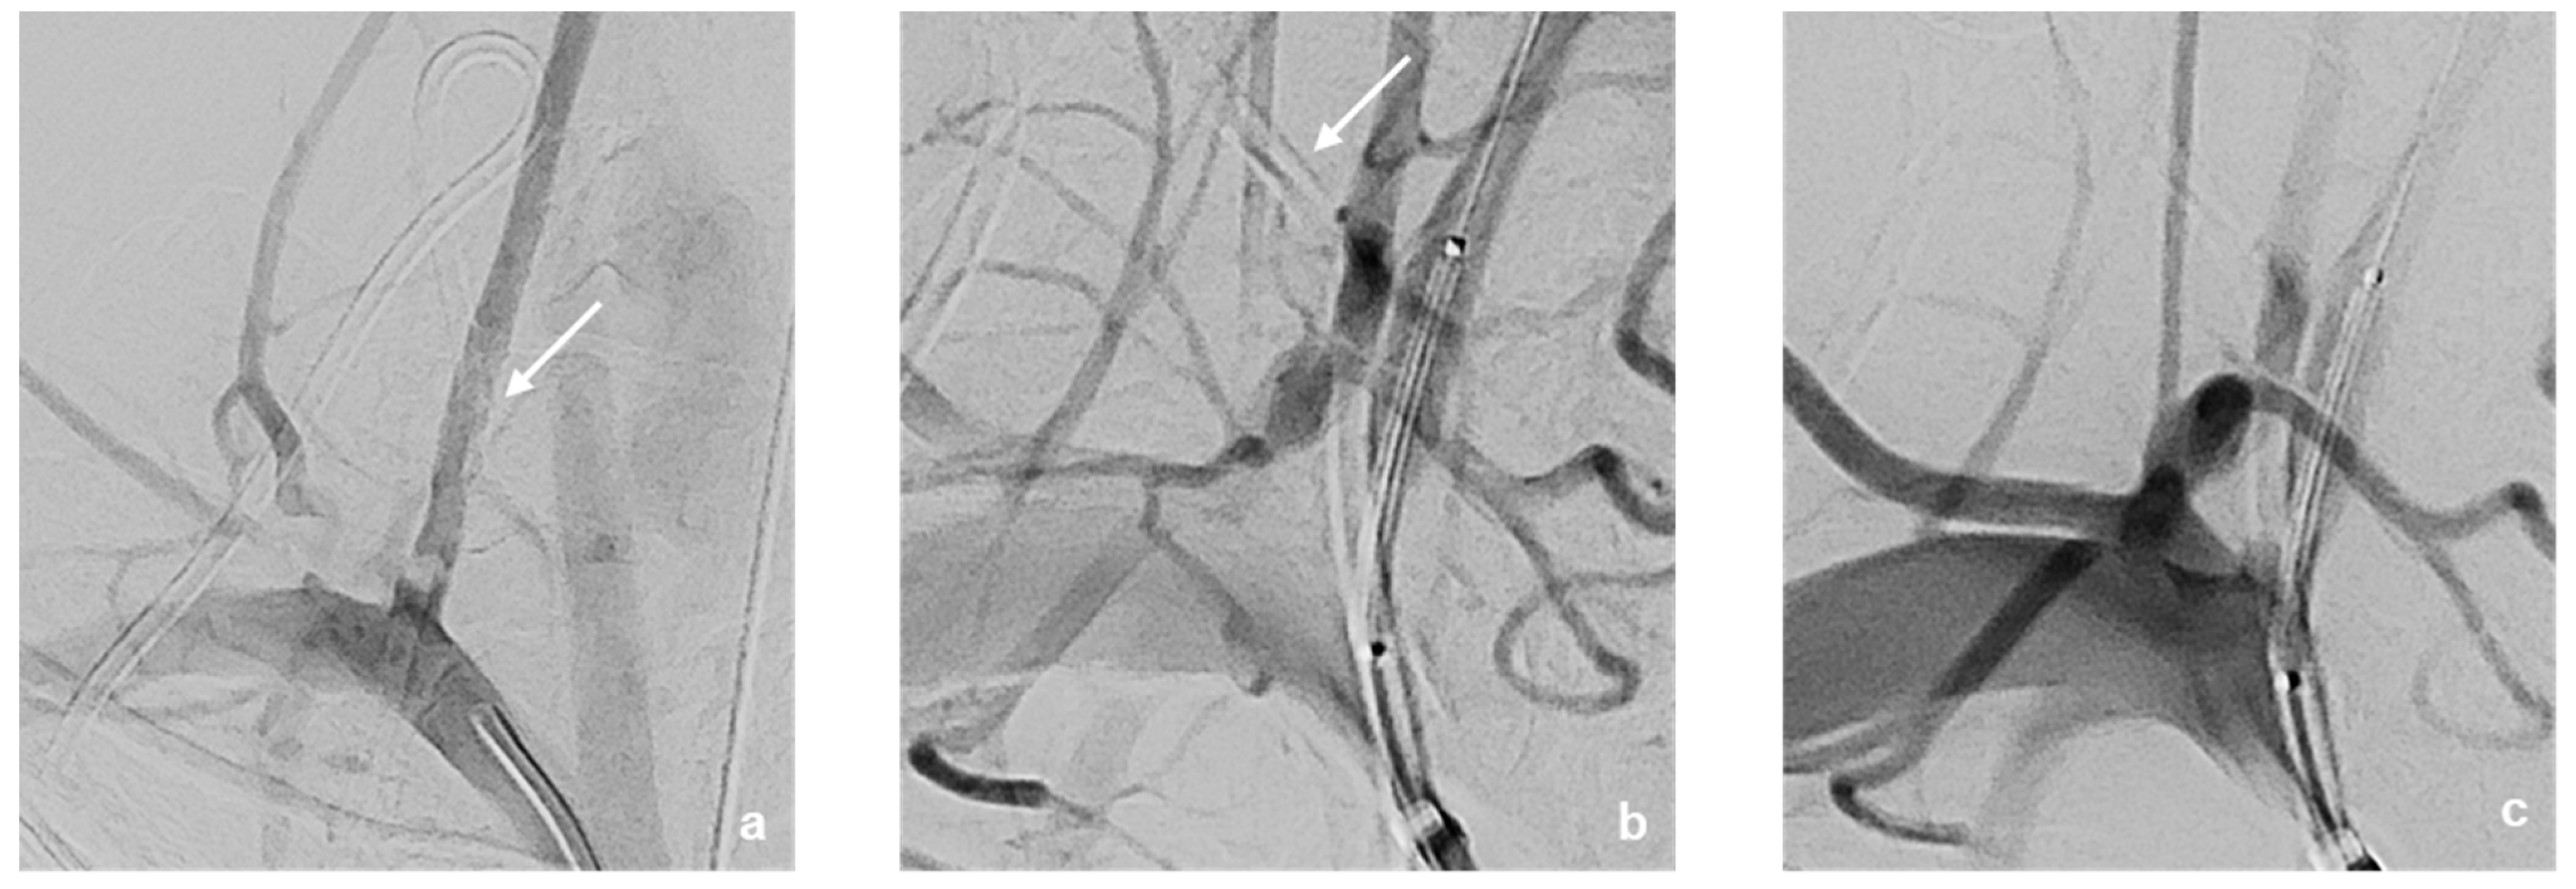

Figure 3. DSA—Imaging findings of the patient at initial presentation (ac). The course of the incorrectly inserted Broviac catheter is indicated by arrows. The Broviac catheter inserted incorrectly into the V0-/V1-segment of the right vertebral artery (a) ends with its tip in the pleural cavity. A BeGraft stent (4.5 mm × 21 mm) was placed directly at the proximal outlet of the right vertebral artery (b,c).

This was followed by selective probing of the right vertebral artery using an 8F Walrus balloon catheter guided via a pORTAL 0.014′ microwire (Figure 3). After checking the correct catheter/wire position, a BeGraft stent (4.5 mm × 21 mm) was positioned but not yet released at the perforation site directly at the proximal outlet of the right vertebral artery (Figure 3b,c). This was followed by careful manual retrieval of the Broviac catheter under fluoroscopic control (Figure 4). After the removal of the Broviac catheter, vascular wall irregularities of the vertebral artery were seen with simultaneous arterial bleeding from the cutaneous access site of the Broviac catheter. Therefore, the indication for implantation of the BeGraft stent was given, which had already been placed in the vertebral artery and could be deployed without technical complications (Figure 5).